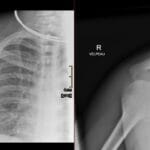

- Radiology Cases: Images with a to-the-point discussion highlighting the specific diagnostic criteria.

- Radiology Spotters: 700+ spot / “Aunt-Minnie” cases divided into sets of 10 each!